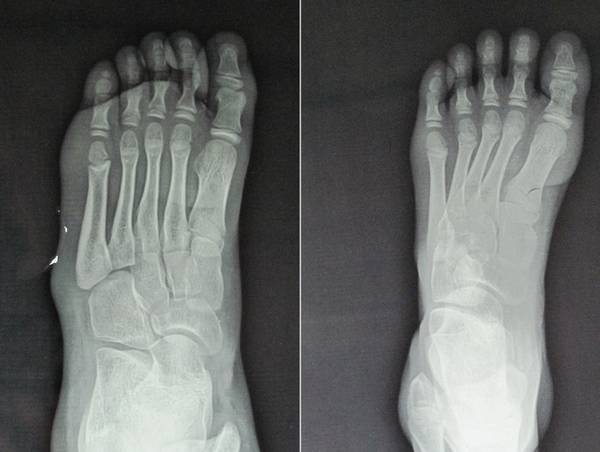

共同讨论一个病例:

半年前患儿洗脚时无意中发现右足踇趾不能伸直,后此症状无变化。

查体:右踇趾下垂,屈曲位不能伸直,被动伸直可,右踇趾感觉正常。右足2-4趾背伸力量减弱,右足2-4趾短伸肌肌腹处未触及肌肉主动收缩。左足伸踇趾及其他足趾伸趾力量减弱。

左踇趾肌力0级

2-5趾4级

右踇趾肌力3级

2-5趾5级弱

小儿神经科会诊,未明确诊断